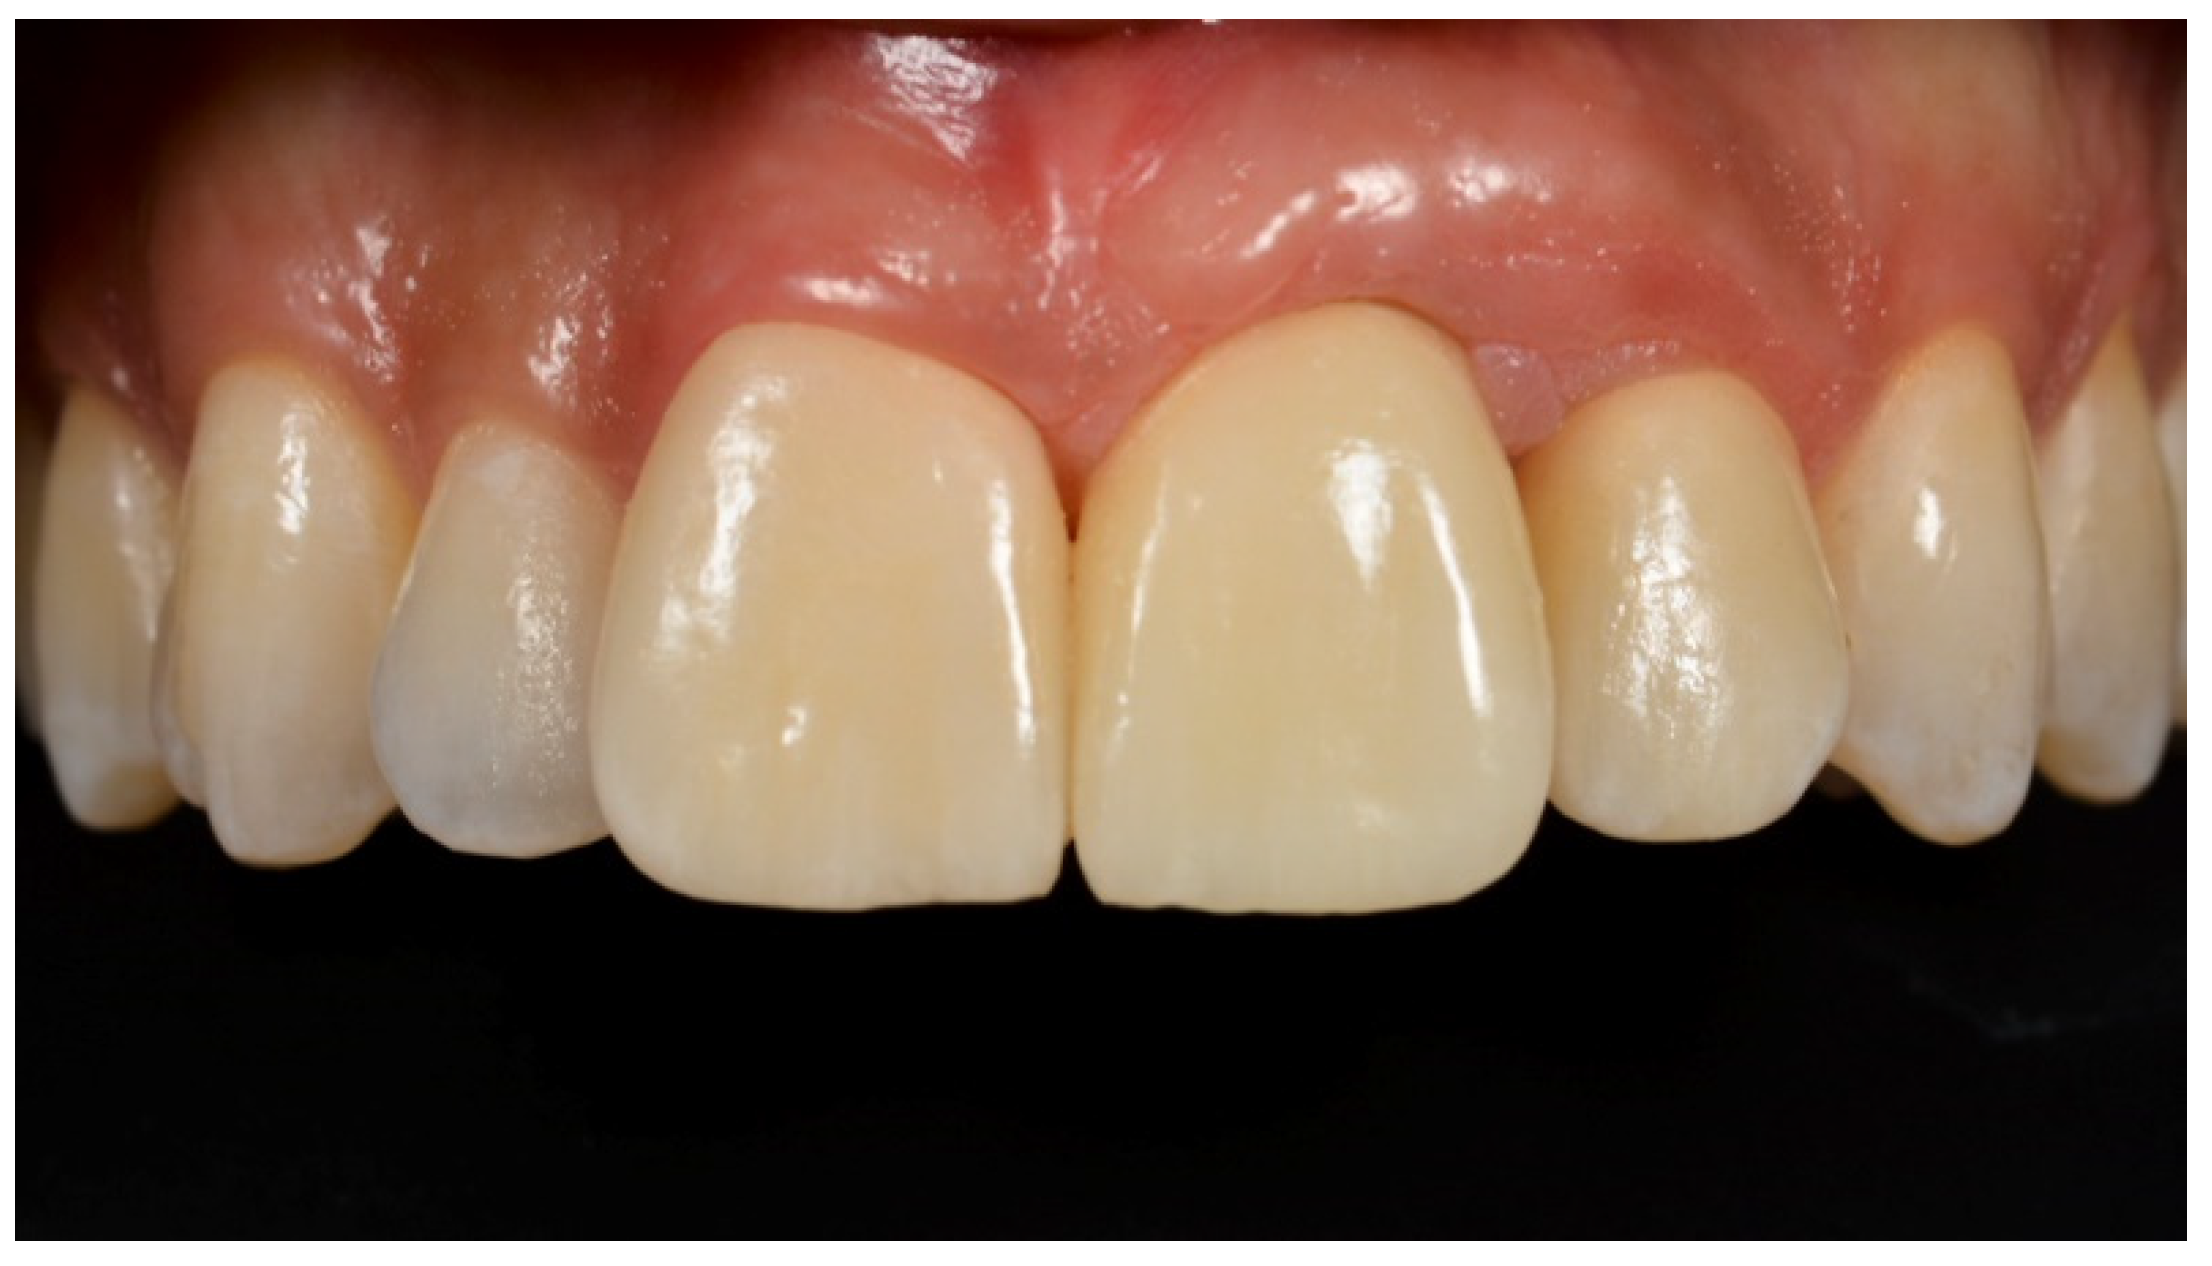

Tissue Recession around a Dental Implant in Anterior Maxilla: How to Manage Soft Tissue When Things Go Wrong?

2. Case Presentation